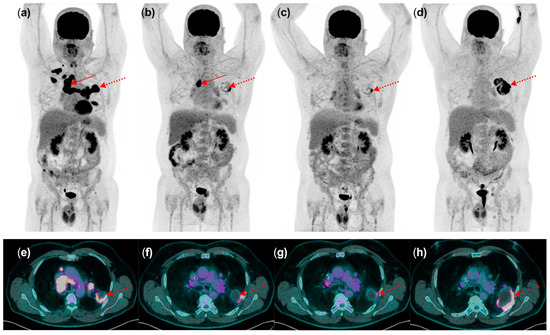

- During the treatment course, interim [18F]FDG PET/CT scans are advised, typically scheduled 8–12 weeks (i.e., 3–4 cycles) after treatment initiation [13]. This is particularly valuable for complementing information obtained from morphological imaging with CT and resolving discordant findings. Differentiating between disease progression and pseudoprogression necessitates a follow-up scan 4–8 weeks later under conditions of clinical stability, underscoring the importance of transparent communication with the treating clinician. Alternatively, a biopsy of the radiographically/metabolically progressive lesion may be warranted. PET/CT scans may also be conducted earlier or later during treatment in instances of clinical deterioration or suspected progression identified in contrast-enhanced CT. It can also guide in the management of dissociated response (DR). DR involves a decrease or stabilization in some tumor sites alongside an increase in others. Although DR is less common, it has been reported in up to 10% of cases treated with ICIs. From a clinical perspective, patients with dissociated response may benefit from treatment beyond progression potentially by continuing checkpoint inhibitor therapy and integrating local treatments, such as surgery, radiotherapy, or interventional radiological treatment of oligoprogressive lesions.

4.2. Insights from a Multidisciplinary Staff Meeting Real-Life Experience: Navigating in the Maze of PPD